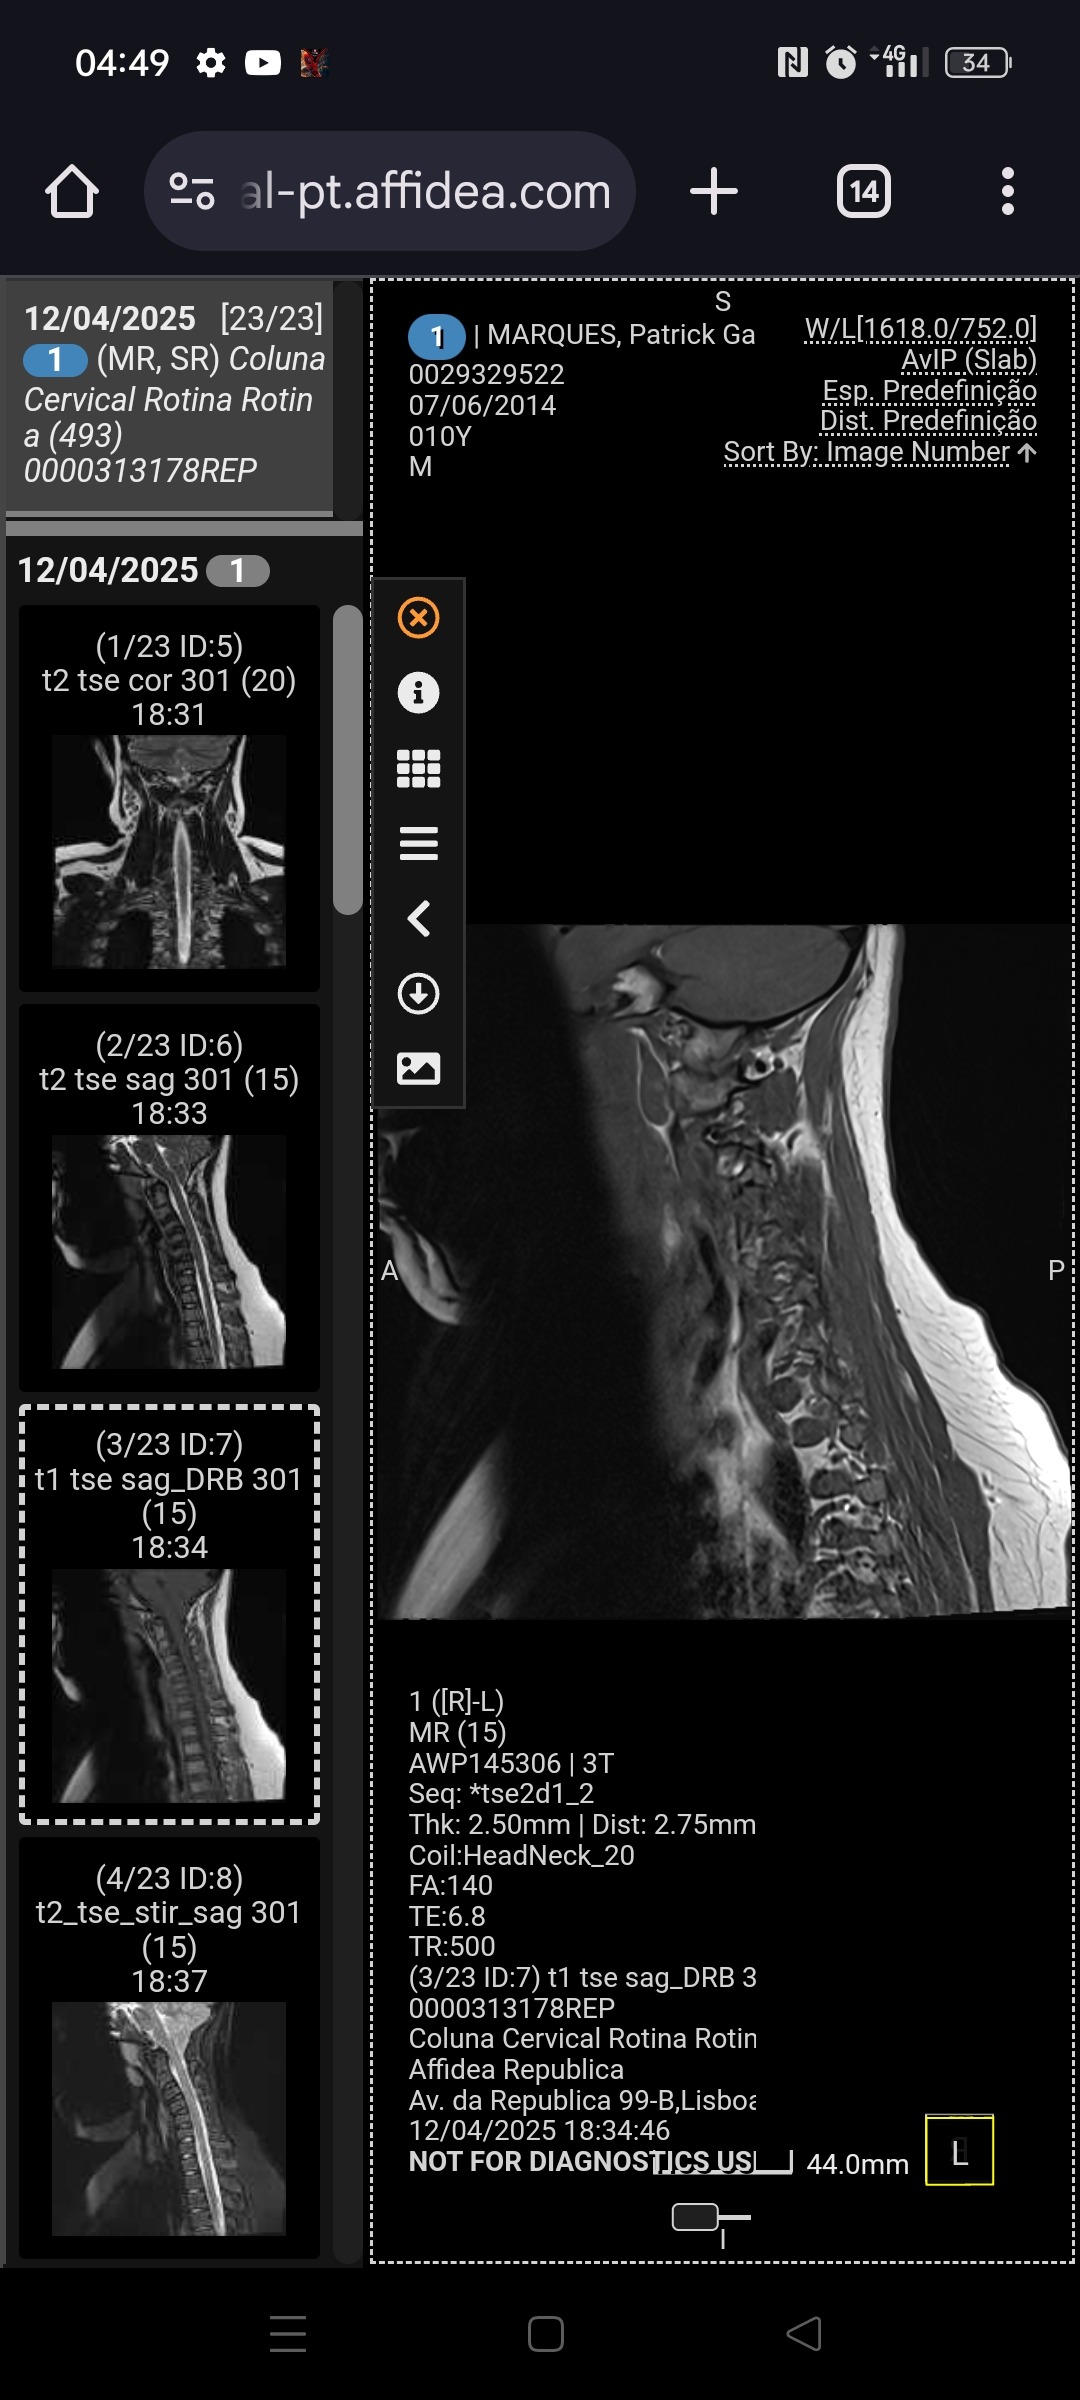

Mas em fevereiro recebemos um diagnóstico difícil: Malformação de Chiari tipo 1, uma condição neurológica que lhe causa dores, tonturas, perda de força e desmaios frequentes.